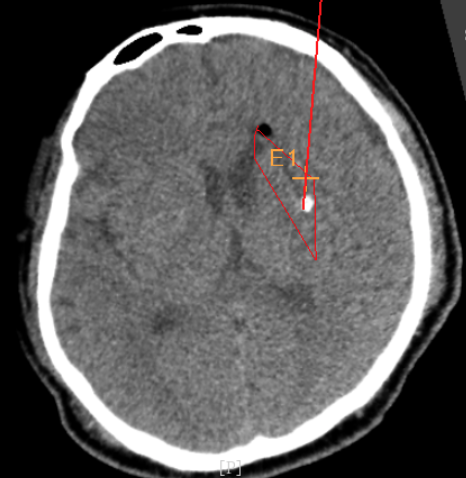

3個月前CT:腦出血

術(shù)前CT:血腫已經(jīng)液化,但仍有占位效應(yīng)